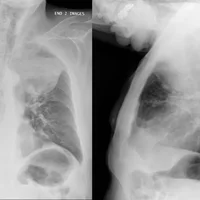

Diagnostic : le diagnostic d’HPP se fait par :

- Examen physique et histoire médicale.

- Tests sanguins pour mesurer les niveaux d'oxygène, de gaz dans le sang et d'autres indicateurs de la fonction hépatique.

- Échocardiogramme pour évaluer la fonction cardiaque et la pression artérielle pulmonaire.

- Cathétérisme cardiaque droit pour mesurer précisément la pression artérielle pulmonaire.